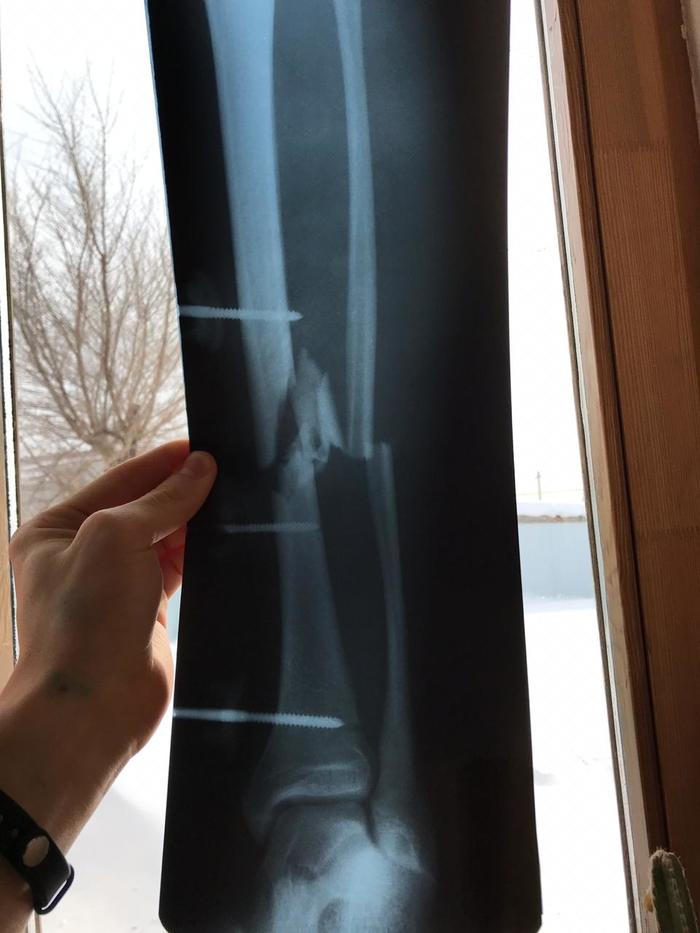

Почти два месяца сотрудник оренбургского батутного клуба «Отрыв» восстанавливается после тяжелой травмы. 22-летний Олег Щарихин во время демонстрационных прыжков на батуте получил открытый перелом голени. Спортсмен рухнул на сетку прямо на глазах у посетителей клуба. Ему оказали первую медицинскую помощь и доставали в больницу на машине скорой помощи. Все это время молодой спортсмен добивается от клуба компенсации или выплаты больничного, но руководство «Отрыва» отказывается признать травму производственной.

Далее два месяца и две сложных операции в ГКБ №4 Оренбурга, но до полного восстановления Олегу еще далеко.

По прогнозам медиков, на реабилитацию спортсмена может уйти около года. Его ногу буквально «собрали» из осколков при переломе голени. Дальнейшая карьера Олега Щарихина под большим вопросом. Он сегодня без работы, в сложном финансовом положении и пока все силы и средства тратит на то, чтобы реабилитироваться после тяжелейшей травмы.